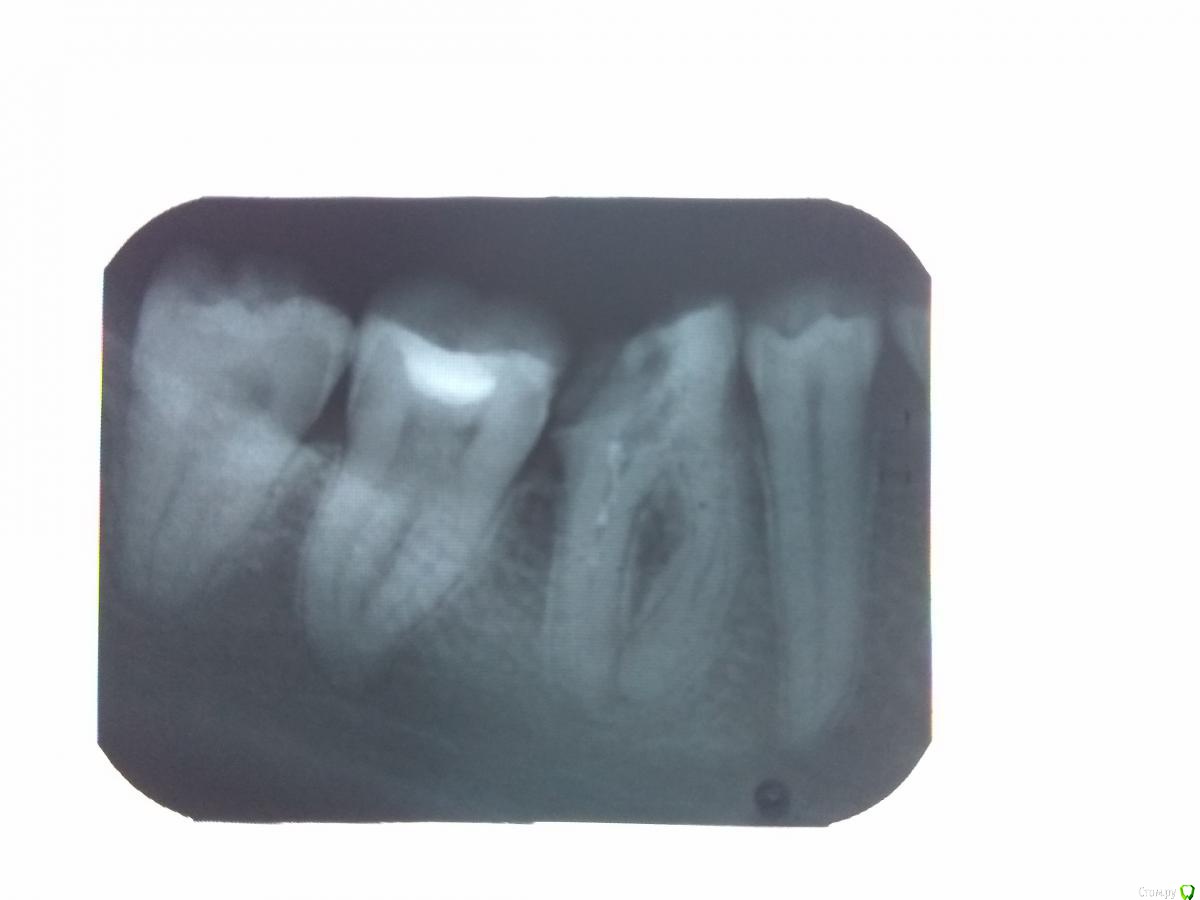

quentin Опубликовано 10 августа, 2017 Поделиться Опубликовано 10 августа, 2017 Добрый день! Подскажите по зубу. Ставили пломбу около 5 лет назад, сейчас пломба разрушилась.В поликлинике предложили поставить штифт и затем коронку.При этом - без гарантий.Еще говорили что-то насчет изменившихся корней (утолщение), что это значит? Есть ли другие варианты?Почему нельзя запломбировать повторно? Ссылка на комментарий

red_butler Опубликовано 10 августа, 2017 Поделиться Опубликовано 10 августа, 2017 Еще говорили что-то насчет изменившихся корней (утолщение), что это значит? Это особенность анатомии вашего зуба. Есть ли другие варианты? Нужно пере лечить корневые каналы и протезировать зуб искусственной коронкой. Альтернатива - удаление зуба. Почему нельзя запломбировать повторно? Почему же нельзя, можно. Но своих тканей осталось так мало, что зуб либо треснет либо сгниет окончательно. При этом - без гарантий. Это мягко говоря, не так. Ссылка на комментарий

St. Опубликовано 10 августа, 2017 Поделиться Опубликовано 10 августа, 2017 В поликлинике предложили поставить штифт и затем коронку. При этом - без гарантий. если не перелечивать каналы , то да. Но я бы не рекомендовала так поступать.Коронку нужно ставить на хороший надежный "фундамент", т.е. адекватно пролеченные каналы Ссылка на комментарий

IvanK Опубликовано 14 августа, 2017 Поделиться Опубликовано 14 августа, 2017 лучше не штифт, а вкладку, проконсультируйтесь с ортопедом Ссылка на комментарий